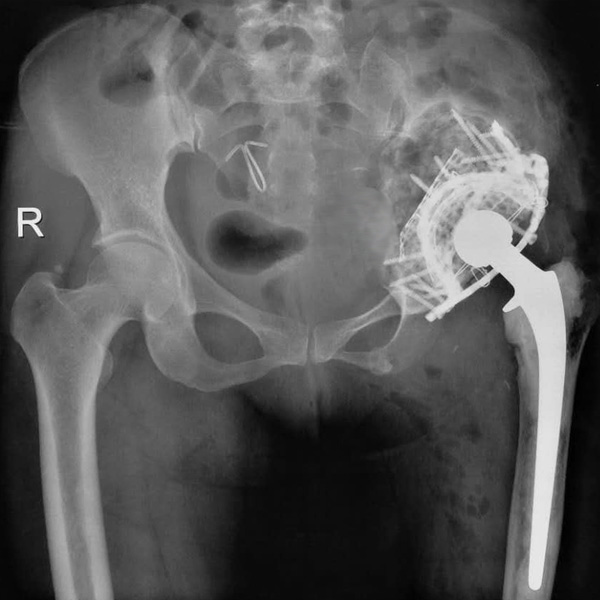

• 骨肉瘤手術骨肉瘤手術手術后手術前

骨肉瘤手術

患者張某,女,14歲,診斷為“左股骨遠端骨肉瘤”,當地醫院因為醫療技術和能力的限制,只能考慮截肢手術。患者家屬通過平臺推薦,指定到哈......